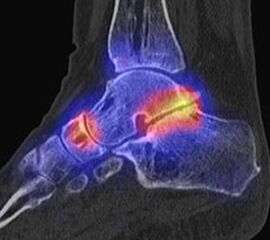

Abbildung 8.2. zeigt den Fall eines Patienten mit Verdacht auf ein knöchernes posteriores Impingement. Es bestanden Beschwerden dorsal bei Plantarflexion und ein Z. n. Distorsion des linken OSG vor 2,5 Jahren. Im MRT 2 Monate vor der SPECT/CT keine wegweisenden Befunde. Im SPECT/CT eindeutige fokal deutliche Mehrspeicherung im Bereich des Processus posterior tali.